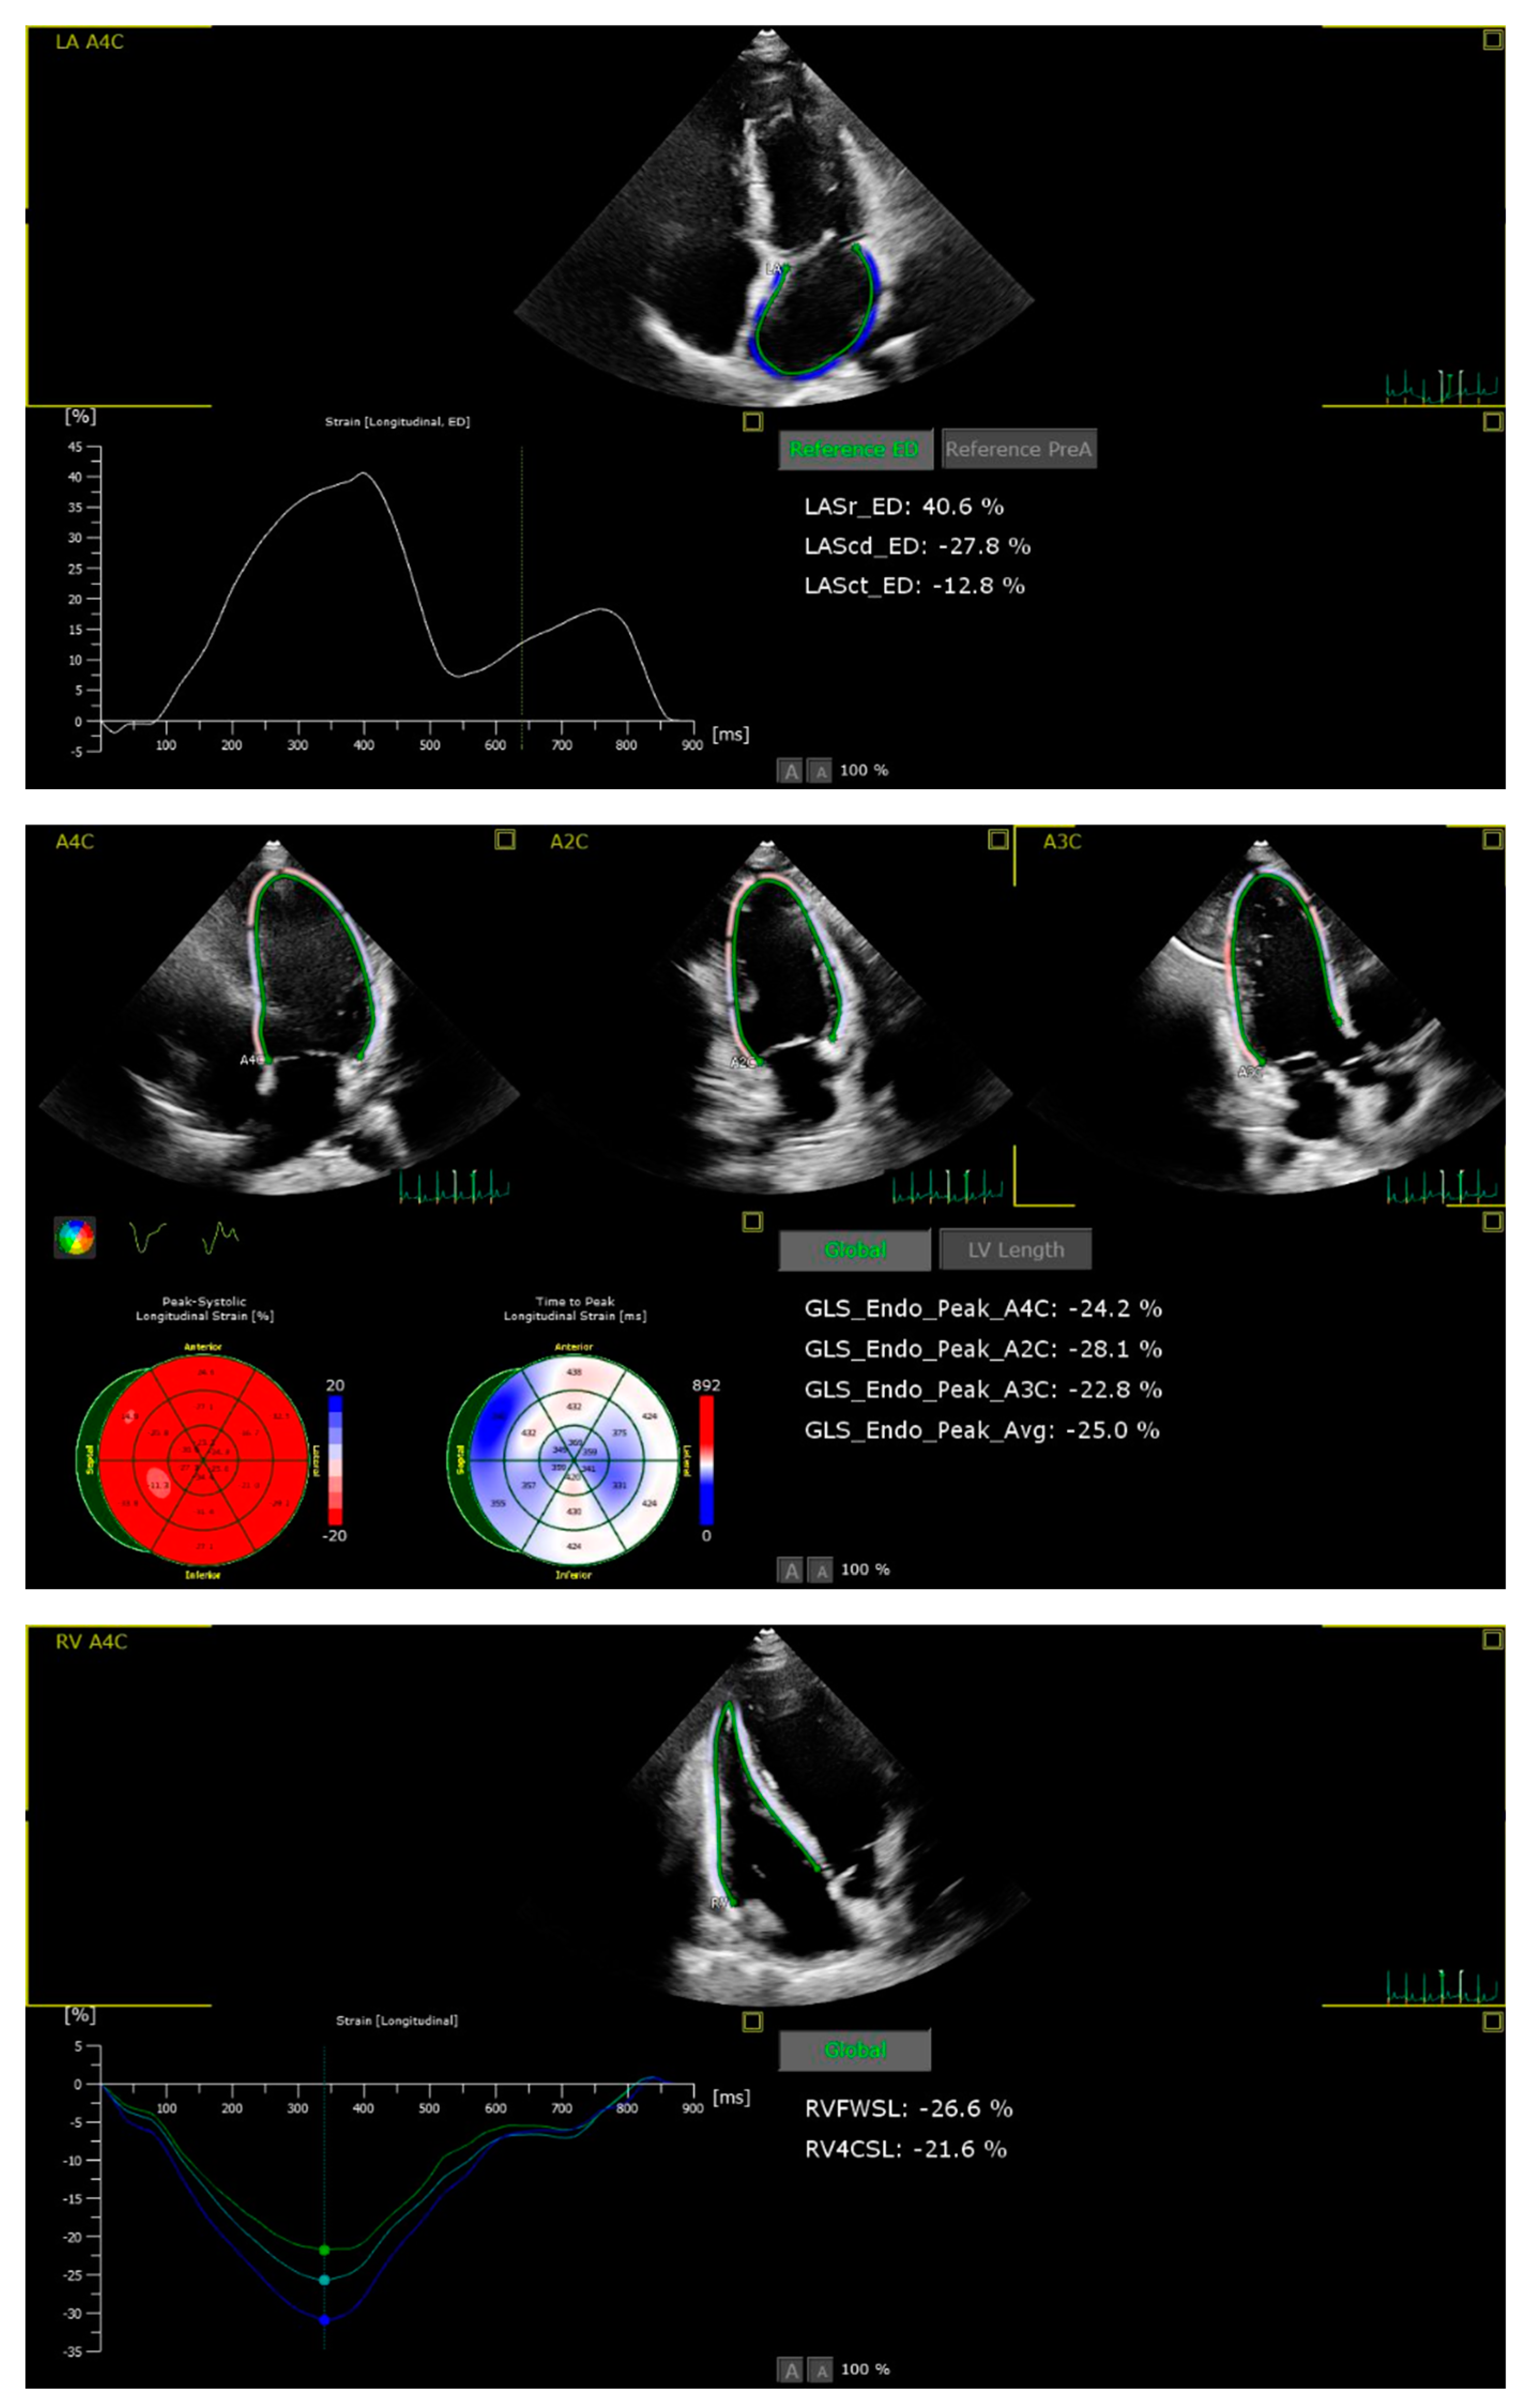

Patients with suboptimal image quality for strain analysis were excluded from the study. The echocardiographic images were analysed by a cardiologist who is particularly interested and trained in cardiovascular imaging and strain echocardiography. The strain values, including the right ventricle GLS (RVGLS) and right ventricle free wall strain (RV-FWSL), the LVGLS, and components of the LAS (atrial reservoir (LAS-r), conduit (LAS-cd), and contractile (LAS-ct) function), were examined from the stored echocardiographic images using a commercially available workstation (QLAB version 13) and by following the recommendations of the EACVI [11] (Figure 1).

Figure 1. Imaging of STE components of left atrial (a), left ventricle (b) and right ventricle strain (c).